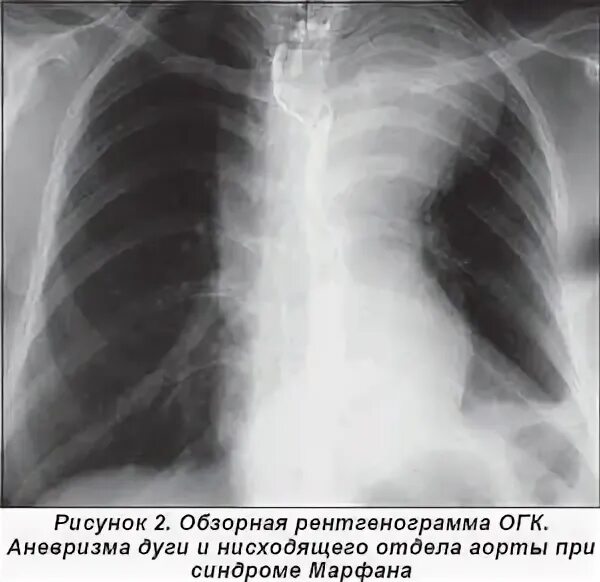

Кальциноз брюшного отдела